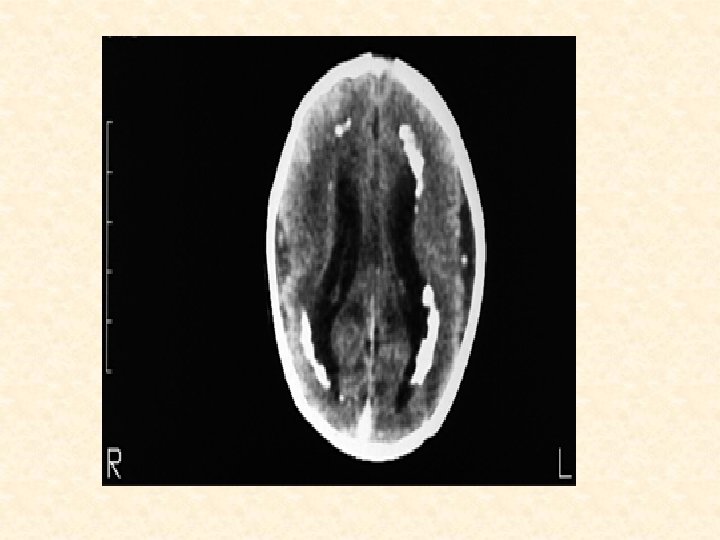

Investigation 1) urine, saliva, blood, CSF for CMV-specific Ig. M 2)PCR 3)CBC - anemia, thrombocytopenia 4)conjugated , unconjugated hyperbilirubinemia 5)elevated hepatic transaminases 6) CSF -- elevated protein content 7) Imaging Studies: CT (Head) - periventricular calcifications Treatment ganciclovir